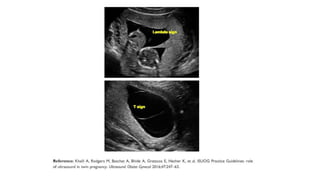

Differences in chorionicity with single placenta

D / D ( fused placenta )

• Monozygotic or dizygotic

• Thick dividing membrane

> 2mm

• Twin peak / lambda sign

M / D

• Monozygotic

• Thin dividing membrane

2mm or less

• T sign

Chorionicity should be determined at the time the twin pregnancy is detected by

ultrasound based upon the number of placental masses, the appearance of the membrane

attachment to the placenta and the membrane thickness. This scan is best performed

before 14 weeks of gestation.[New 2016] (B)